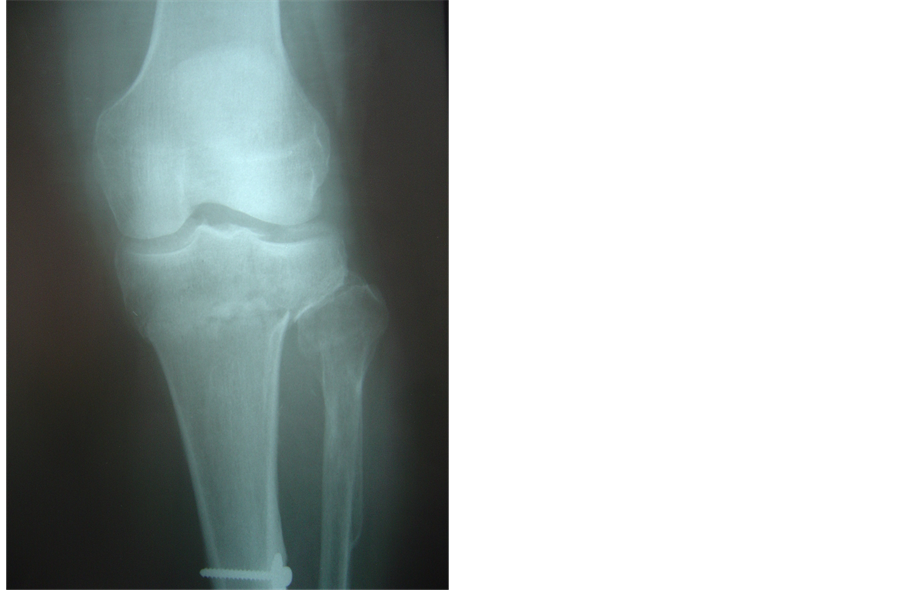

Figure 3. (a), (b): Schatzker VI fracture. Pre operative X-rays AP and Lateral; (c), (d): The fracture was treated with combination of canulated screw and anatomic locking plate because of presence of previous metal ware. Post-operative X-rays AP and lateral.

In three of our cases a hybrid fixator could not be used because of previous tibial shaft fractures that had been treated with open reduction and internal fixation―the presence of metal ware forbidding application of peripheral pins. In these cases, we chose to combine canulated screws with an anatomic lateral plate. Here, the canulated screws were applied open, through a lateral incision, but extremely close to the articular surface to allow correct positioning of the anatomic locking plate. The knee was once more not opened and the plate applied to unite the condyles to the shaft. Careful correction of varus-valgus malalignement and accurate canulated screw positioning were always checked with the II (Figures 3(a)-3(d)).